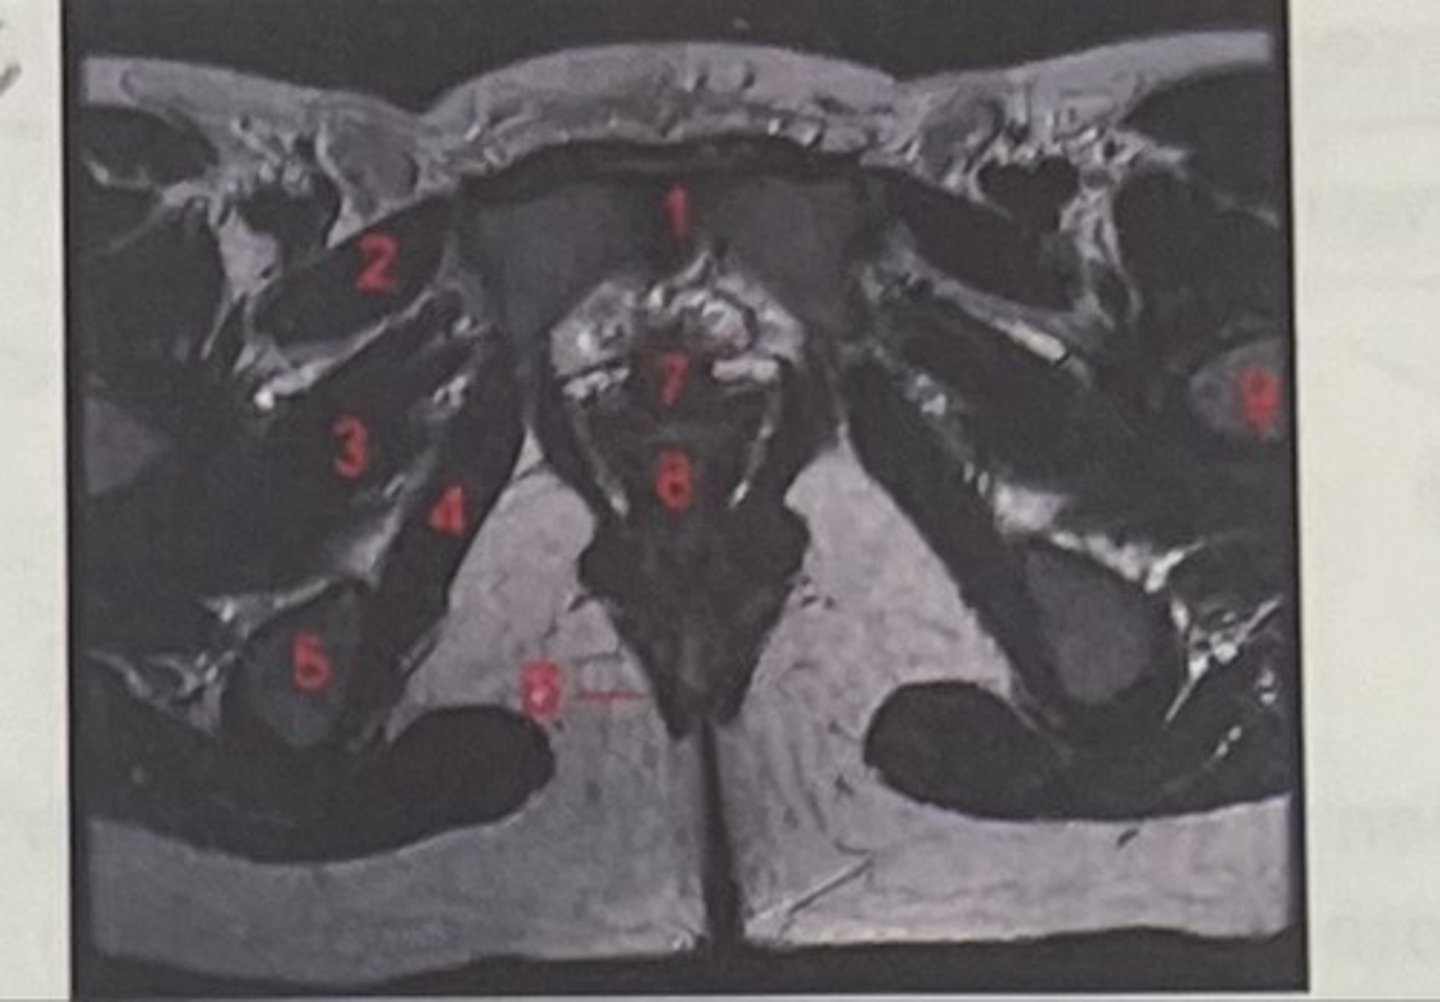

pubic symphysis

What is 1

Pectineus

What is 2

Obturator externus

What is 3

obturator internus

What is 4

ischial tuberosity

What is 5

external spincter

What is 6

Urethra

What is 7

Vagina

What is 8

Femoral nerve

What is 9

Left lung